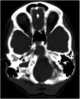

Osteolytic metastasis

Bone metastases, or osseous metastatic disease, is a category of cancer metastases that results from primary tumor invasion to bone. Bone-originating primary tumors such as osteosarcoma, chondrosarcoma, and Ewing's sarcoma are rare. [Source: Wikipedia ]